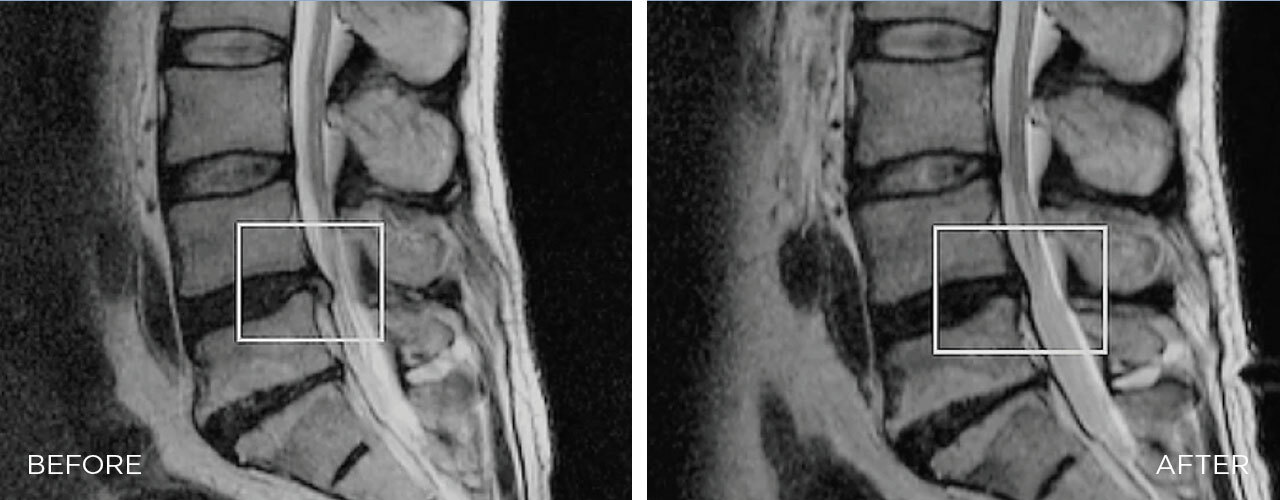

EFFICACY OF SPINAL DECOMPRESSION THERAPY IN INDIVIDUALS WITH LUMBAR DISC HERNIATION – A RANDOMIZED CONTROLLED TRIAL

The BTL SPINAL DECOMPRESSION is a mechanical therapy that uses automated decompressive forces to mobilize joints, relieve the pressure over neuro-spinal structures, and relax and elongate soft tissues.

The therapy is based on the targeting decompressive forces applied over vertebrae. Decompressive forces occur as automated and controlled cycles which leads to enlargement of intradiscal spaces, enhanced blood perfusion, disc rehydration, and realignment of vertebrae.Â